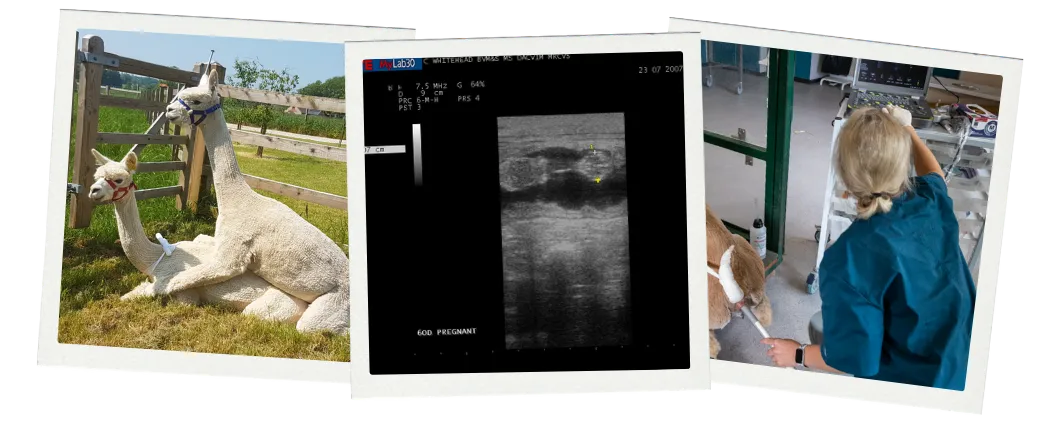

Part 2 Pregnancy & Pregnancy Diagnosis

In this section, we discuss the physiology of pregnancy, and the different tools we can use to diagnose pregnancy. We discuss the implications of physiology on breeding and an ideal reproductive plan for breeding females.

In this module we cover the importance and practice of pregnancy diagnosis, care of the pregnant female, routine herd health procedures for pregnant females and preparing yourself and your herd for neonatal care.